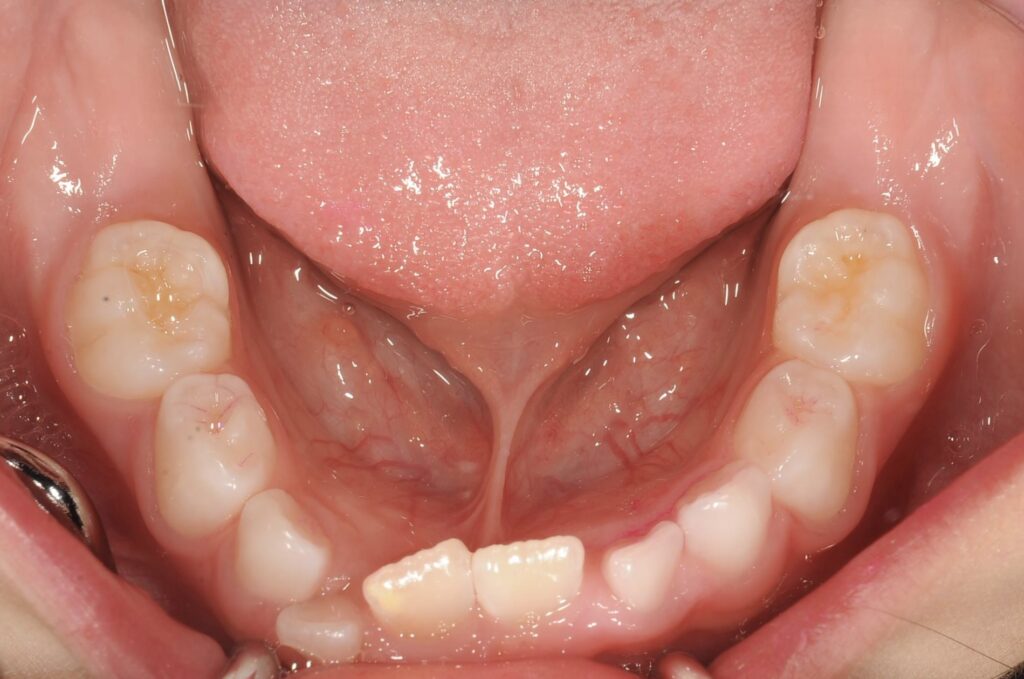

5歳 女児 小児矯正

歯並びの状態:

叢生(ガタガタ)

過蓋咬合(咬み合わせが深い)

BEFORE

AFTER

主訴

右下の歯が飛び出ているので治したい。

診断名・主な症状

過蓋咬合

治療内容

上下の歯並びの幅を拡げつつ、前歯の関係を改善しました。

治療期間

2年 + 後戻り止め期間(5年)

通院回数

25回

費用

50万円程度(税別)